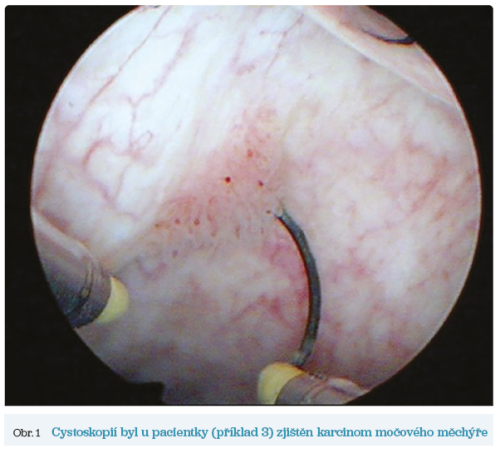

Čtyři zajímavé kazuistiky z urologické praxe přináší MUDr. Lukáš Horčička, Ph.D. (str. 156–157), farmakoterapii se věnují prof. MUDr. Jitka Mlíková Seidlerová, Ph.D. (arteriální hypertenze, str. 158–160) a prof. MUDr. Hana Rosolová, DrSc., FESC (dyslipidemie, str. 162–164).